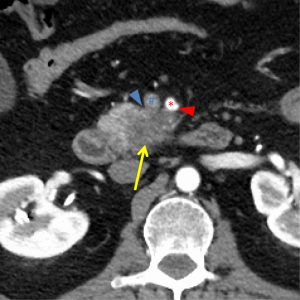

The first and most critical step in the management of PC is the determination of the clinical stage of disease and establishment of a histologic diagnosis. All disease-specific and stage-specific treatment planning is predicated on this step. With PC, it is critically important to use standardized, objective radiologic criteria for clinical staging. Modern imaging techniques have revolutionized the clinical staging of PC. Before the development of multidetector CT, up to 30% of patients with presumed resectable PC were found, at the time of operation, to have either metastatic disease or local tumor-associated vascular invasion which precluded resection (28). Currently, precise and objective anatomic radiographic criteria are used to determine the extent of the tumor-vascular relationship and to categorize clinical staging (Table 3). PC can be broadly divided into patients with inoperable disease (metastatic or locally advanced) and operable disease [borderline resectable (BLR) or resectable]. The majority of patients will present with metastatic disease, as evidenced by ascites/peritoneal implants, liver, or lung metastases. In the absence of metastatic disease, the clinical stage is determined by the relationship of the primary tumor to adjacent vasculature. As a general rule, any tumor abutment (≤180 degree tumor-vessel interface) or encasement (>180 degree) of the celiac axis, common hepatic artery, or SMA should be considered a contraindication to immediate surgery. A patient is deemed to have locally advanced, unresectable disease when: (I) the tumor encases the SMA or celiac axis, as defined by >180 degrees of the circumference of the vessel; or (II) there is occlusion of the SMPV confluence without the possibility for venous reconstruction (Figure 1). Patients who have tumor abutment, without encasement, of the SMA or celiac axis, or short segment encasement of the hepatic artery are considered to have BLR PC (Figure 2) (29). In addition, patients with tumors that cause >50% narrowing or short segment occlusion of the SMV/PV that may be amenable to reconstruction are also considered to be BLR. There is emerging consensus that even more subtle tumor-vein abutment may be best considered BLR, especially with respect to the use of neoadjuvant therapy rather than surgery-first (30). Finally, patients who have radiographic lesions which are indeterminate for metastases (usually too small to accurately characterize), even in the absence of SMA abutment or venous narrowing, are also considered by some institutions to have BLR PC (31). Radiographic findings of a resectable PC are (I) the absence of tumor-arterial abutment or encasement; and (II) <50% narrowing of the SMV/PV (Figure 3).